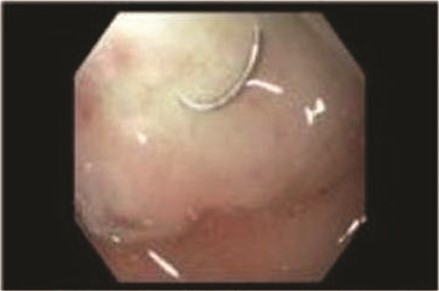

A 56-year-old African American male presented in 2015 with abdominal pain, with associated melena and hematochezia. The patient has a history of chronic back pain for which he takes 600 mg ibuprofen daily, alcohol abuse, tobacco use and a previous GI bleed in 2011, which necessitated 6 units (U) of packed red blood cells (PRBCs) and emergency therapeutic endoscopy. The patient was found to be hypotensive to 76/56 mm Hg, and hemoglobin (Hgb) was found to be 9.4 g/dl, from a previous baseline of 10.6 g/dl. His rectal examination was guaiac positive. A repeat Hgb was found to be 6.5 g/dl. The patient was given 3 U of PRBC and an emergency endoscopy was performed. On endoscopy, the patient was found to have a 6 cm gastric ulcer with an associated vessel underneath of a large clot. Due to the high risk nature of the bleed, it was felt by the gastroenterologist that the patient should undergo an endovascular angioembolization (Fig. 1). The patient was brought to the Interventional Radiology Suite for the procedure. The patient’s right common femoral artery was accessed and the celiac trunk was selected. A subselective common hepatic arteriogram was performed, which demonstrated active extravasation arising from the proximal aspect of the GDA. The GDA was then coil embolized both proximal and distal to the site of bleeding using five microcoils. Repeat arteriogram demonstrated no further opacification of the GDA and no further extravasation (Fig. 2).

Demonstrating coil embolization of the GDA with no opacification